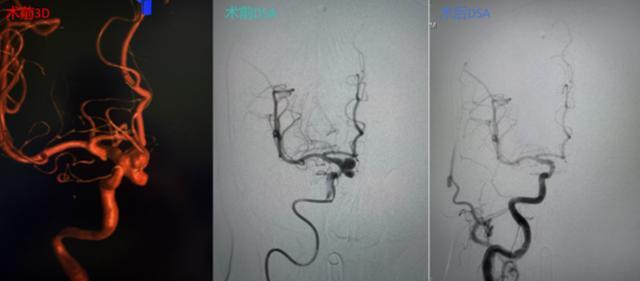

在与家属充分沟通并获得同意后,手术团队制定了周密的手术方案。手术中,专家凭借精湛的微导管超选技术在桡动脉建立通路,在复杂迂曲的血管中“翻山越岭”,精准抵达右侧颈内动脉,成功避免路经主动脉弓。

面对宽颈动脉瘤的难题,团队巧妙运用支架辅助栓塞技术,将一根根弹簧圈严密填塞入动脉瘤囊内。术后即刻造影显示,动脉瘤腔内血流消失,载瘤动脉通畅无阻,手术取得圆满成功,患者已康复出院。